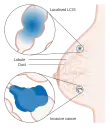

عوامل خطرساز جهت ابتلا به سرطان پستان شامل جنسیت مؤنث، چاقی، عدم فعالیت بدنی، الکلیسم، درمان جایگزینی هورمون پس از یائسگی، پرتوهای یونیزان، منارک زودهنگام (آغاز قاعدگی) در سنهای پائینتر، دیر بچهدار شدن یا عدم بارداری، سابقهٔ قبلی سرطان پستان و سابقهٔ خانوادگی سرطان پستان است.[1][2] در حدود ۵–۱۰٪ موارد زمینهٔ ژنتیکی و از والدین به ارث میرسد[1] که میتوان به جهشهای ژنی BRCA1 و BRCA2 اشاره کرد.[1] منشأ بیشتر سرطانهای پستان از سلولهای جدار مجاری شیر و لوبولهای شیرساز است.[1] به آنهایی که از مجاری شیری نشأت میگیرند «کارسینوم درجای مجاری پستان» و به آنهایی که از کیسههای کوچک شیرساز نشات میگیرند، «کارسینوم لوبولار» میگویند.[1][9] در حدود ۱۸ زیرگروه از سرطان پستان وجود دارد.[2] برخی از آنها نظیر «کارسینوم درجای مجاری» از رشد و تکامل ضایعات پیشسرطانی ناشی میشوند.[2] تشخیص سرطان پستان از طریق انجام بیوپسی از بافت مشکوک امکانپذیر است.[1] وقتی تشخیص قطعی شد، آزمایشهای دیگری انجام میشوند تا معلوم شود آیا سلولهای سرطانی به بیرون از پستان نیز گسترش یافتهاند یا خیر. و همچنین کدام روش درمانی مؤثرتر خواهد بود[9].[1]

عوامل خطر ابتلاء به سرطان پستان عبارتند از مرض چاقی، عدم تمرین فیزیکی، نوشیدن نوشیدنیهای الکلی، درمان جایگزینی هورمون در طول یائسگی، پرتوهای یونی، اولین قاعدگی در سنین پایین، و دیر بچه دار شدن یا بچه دار نشدن.[1][2] دلیل حدود ۵ تا ۱۰٪ از موارد ابتلاء به این بیماری ژنهایی هستند که از والدین فرد به ارث رسیدهاند، از جمله BRCA1 و BRCA2. معمولاً سرطان پستان در سلولهای دیواره مجاری شیر و لوبولها که تأمینکننده شیر مجاری هستند، ایجاد میشود.به سرطانهایی که از این مجاری شروع میشوند، کارسینوم پستان گفته میشود، در حالیکه سرطانهای ایجاد شده از لوبولها با نام سرطان لوبولار شناخته شدهاند.[1] به علاوه، بیش از ۱۸ زیر-نوع سرطان پستان دیگر وجود دارد.برخی از سرطانها از ضایعات پیش-تهاجمی از قبیل کارسینوم مجرایی درجا ایجاد میشوند.[2] تشخیص سرطان پستان با انجام یک نمونه برداری از توده مربوط تأیید میشود.پس از تشخیص سرطان، آزمایشهای بیشتری انجام میشوند تا مشخص شود که آیا سرطان به قسمتهای دیگر بدن نیز سرایت کردهاست یا خیر و چه درمانهایی ممکن است نسبت به بیماری واکنش نشان دهند.[1]